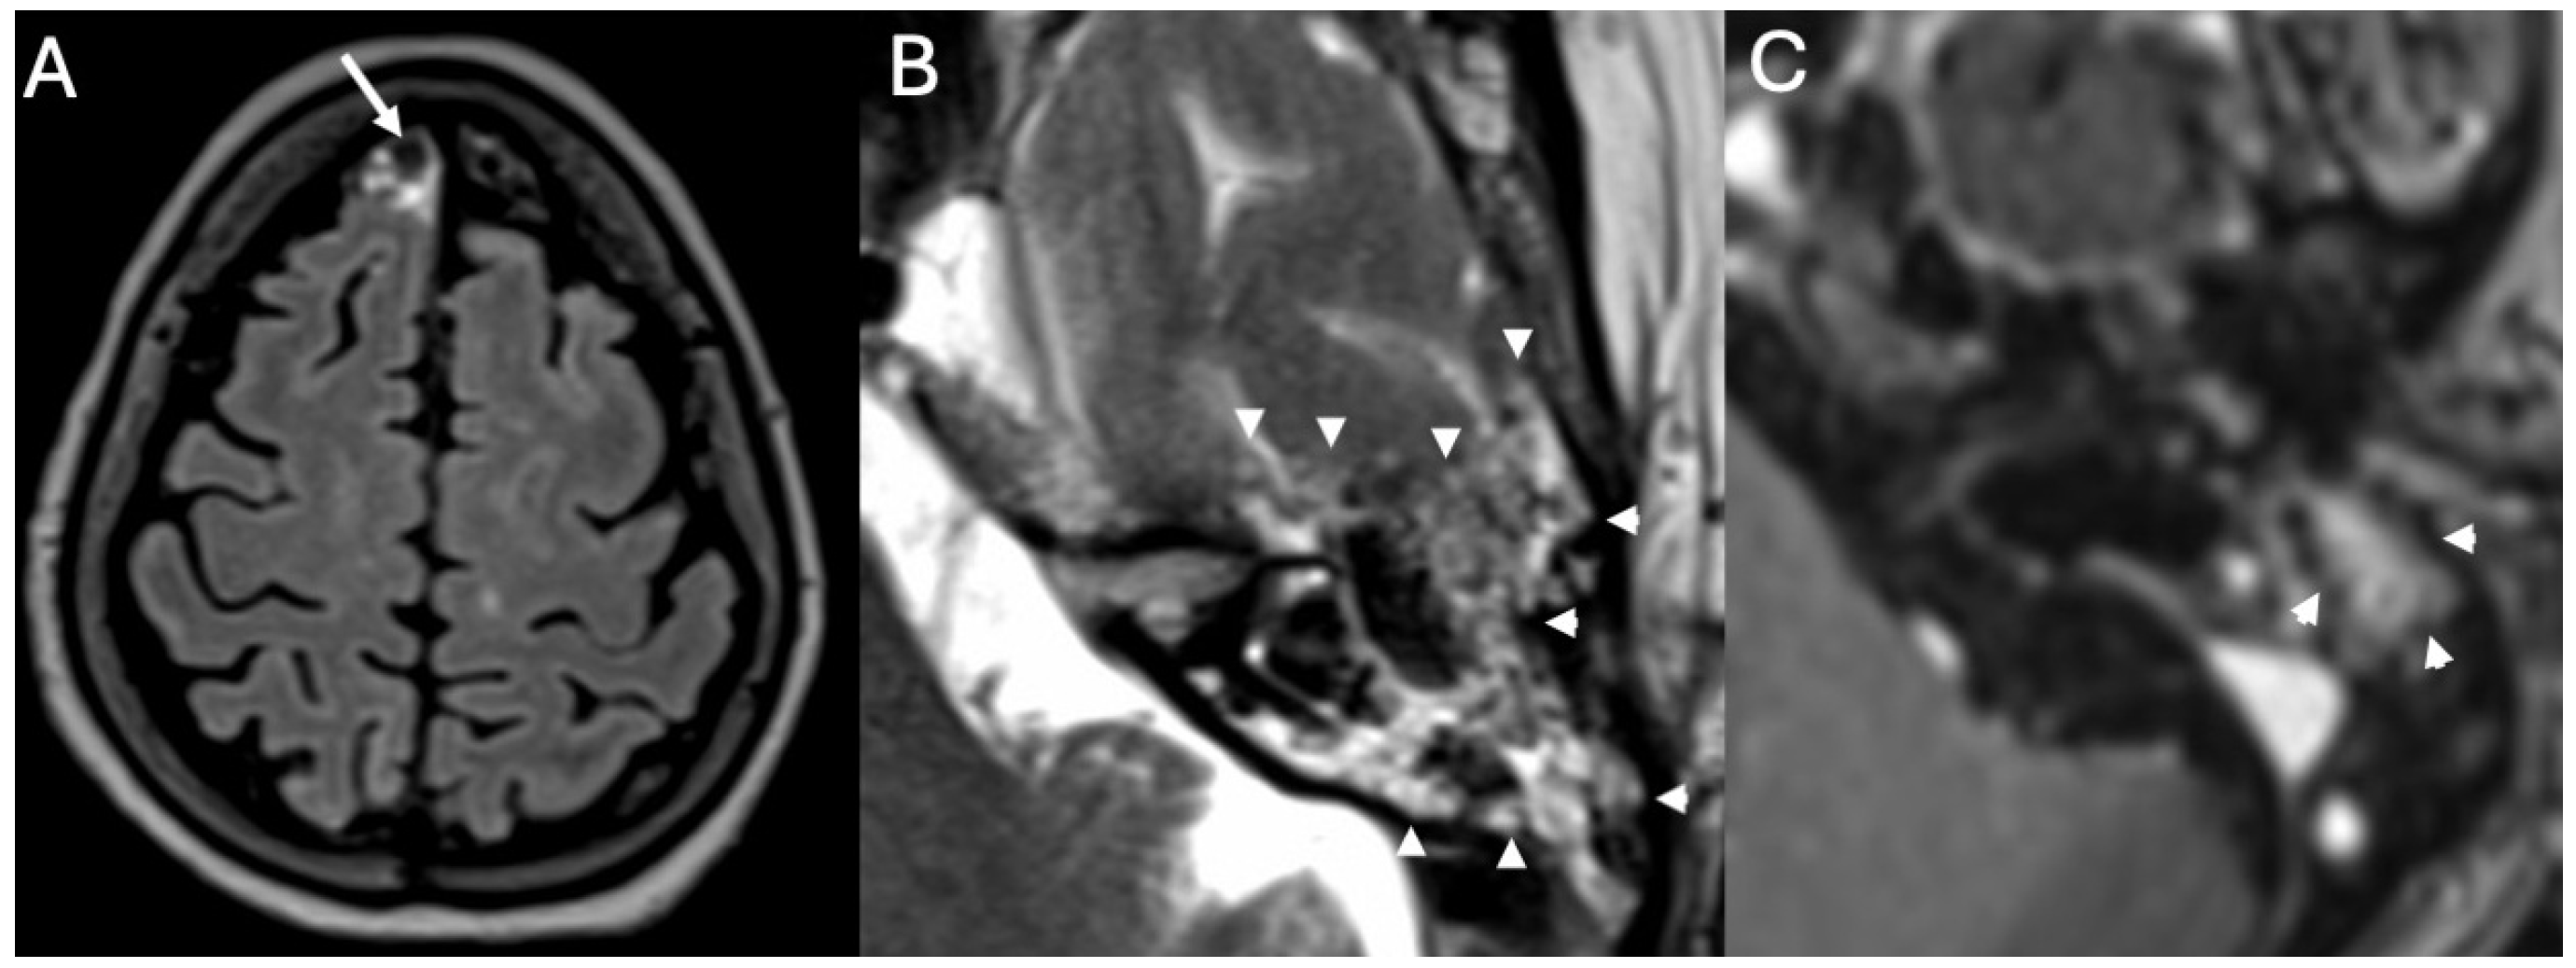

3.4. Labyrinthitis and Vestibulocochlear Neuritis

Imaging

3.5. Cochlear Hemorrhage

| Labyrinthitis/Vestibulocochlear Neuritis | Taxak & Ram 2020 [32]; Kharrat et al., 2024 [33]; Singh et al., 2023 [34]; Kim et al., 2024 [35] | Case reports and small series | Meningitis can cause secondary labyrinthitis with cochlear enhancement on MRI; progression to ossification possible if chronic. |

| Cochlear Hemorrhage (Rare Complication) | Perillo et al., 2024 [36]; Engelen-Lee et al., 2016 [37] | Case report; pathologic correlation study | First documented case of cochlear hemorrhage secondary to pneumococcal meningitis; likely due to microvascular injury. |